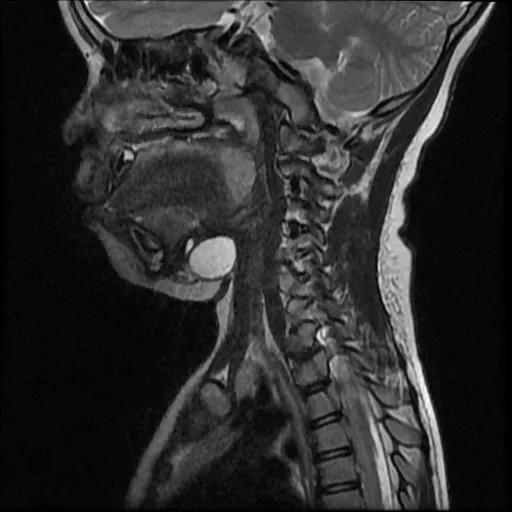

甲状舌管囊肿 MRI 矢状位图像

重庆北部宽仁医院耳鼻咽喉科刘蓉蓉主任接诊后,经过高分辨率磁共振检查,再次证实了小新患甲状舌管囊肿的诊断,基本排除「异位甲状腺」等可能性。同时发现小新的囊肿与舌骨粘连紧密,有瘘管一直向上发展与舌盲孔相通,完整切除包块的难度比预想中要大。